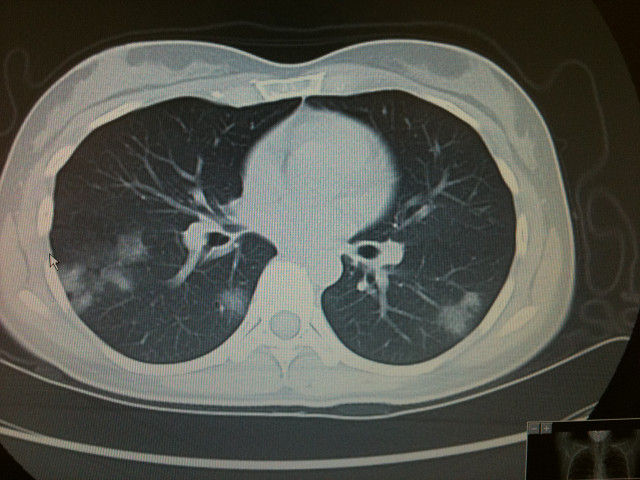

特発性器質化肺炎の胸部ct画像 左の肺(写真の右側)に肺炎のような陰影がみられます 日本呼吸器学会では学会ホームページにて「のみなさま向」に様々なコンテンツを公開しています 。. 26 日本内科学会雑誌 第103巻 第11号・平成26年11月10日 Ⅱ.診断法の進歩 1.呼吸器感染症の画像診断 氏田万寿夫1) 佐藤 英夫 2)山口美沙子 要旨 市中肺炎でみられる画像パターンは気腔性肺炎と気管支肺炎パターンに大別され,肺野末梢の非区域性. Dec 5, 18 第48回城南・早良・西区胸部画像勉強会 ~器質化肺炎とは~.

器質化肺炎パターン 要 旨 新型コロナウイルス(covid-19)肺炎は、パンデミック後世界的に市中肺炎化してきている。我々は、ク ルーズ船内でcovid-19に感染し、入院当初、無症状であったが、胸部ct で肺炎像が確認された2 例を経 験した。. CT Features of Coronavirus Disease 19(COVID-19) Pneumonia in 62 Patients in Wuhan,China. 器質化肺炎(OP:organizing pneumonia)を起こす原因とCT画像診断についてまとめました。 中でも原因不明なのが、特発性器質化肺炎(COP)です。 目次1 器質化肺炎(OP:organizing pne ….

Respiratory bronchiolitis – associated interstitial lung disease. Consolidaionがみられる。ウイルス性肺炎の他に、抗 菌薬不応性の特発性器質化肺炎や膠原病、血管炎など を背景とする間質性肺炎などが鑑別にあがり、確定診 断のため気管支肺胞洗浄や生検などが実施される場 合もある経過と画像所見であった。. • 石灰化 – 結節全体・中心部・ポップコーン状石灰化は良性 • 辺縁の性状 – Spicula,notchは悪性で見られるが良性でも • 造影効果 – 15HU以上の造影効果は悪性を指示、但しそれぞれに例外が 器質化肺炎、、 大細胞癌、、 • 周囲の散布像.